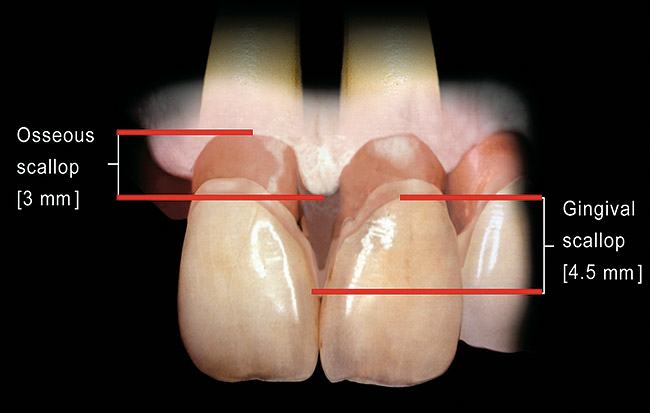

The real challenge when removing the two centrals is to evaluate what happens to the papilla between them after extraction.9,10 Before extraction, the osseous crest around both centrals, assuming no periodontal disease exists, roughly follows the scalloped nature of the cementoenamel junctions (CEJs) as they flow from the facial into the interproximal, resulting in an average osseous scallop of 3 mm; the average interproximal bone height is 3 mm coronal to the facial crest of bone. Because the soft tissue typically follows the scallop of the bone, the osseous scallop results in a gingival scallop of 3 mm. However, when teeth are present, an interesting phenomenon occurs. The gingiva on the facial of the tooth is positioned so that, on average, the free gingival margin is 3 mm coronal to the crest of bone. However, the interproximal papilla between teeth is positioned, on average, 4.5 mm coronal to the interproximal crest of bone, 1.5 mm, on average, more coronal to the crest of bone than is the facial tissue. This additional 1.5 mm, along with the 3 mm average osseous scallop, results in the tip of the papilla being an average 4.5 mm to 5 mm coronal to the facial free gingival margin (Figure 2).

Figure 2  Between natural teeth, the average osseous scallop is 3 mm from the facial to the interproximal, and the average gingival scallop is 4.5 mm from the facial to the interproximal.

Figure 2